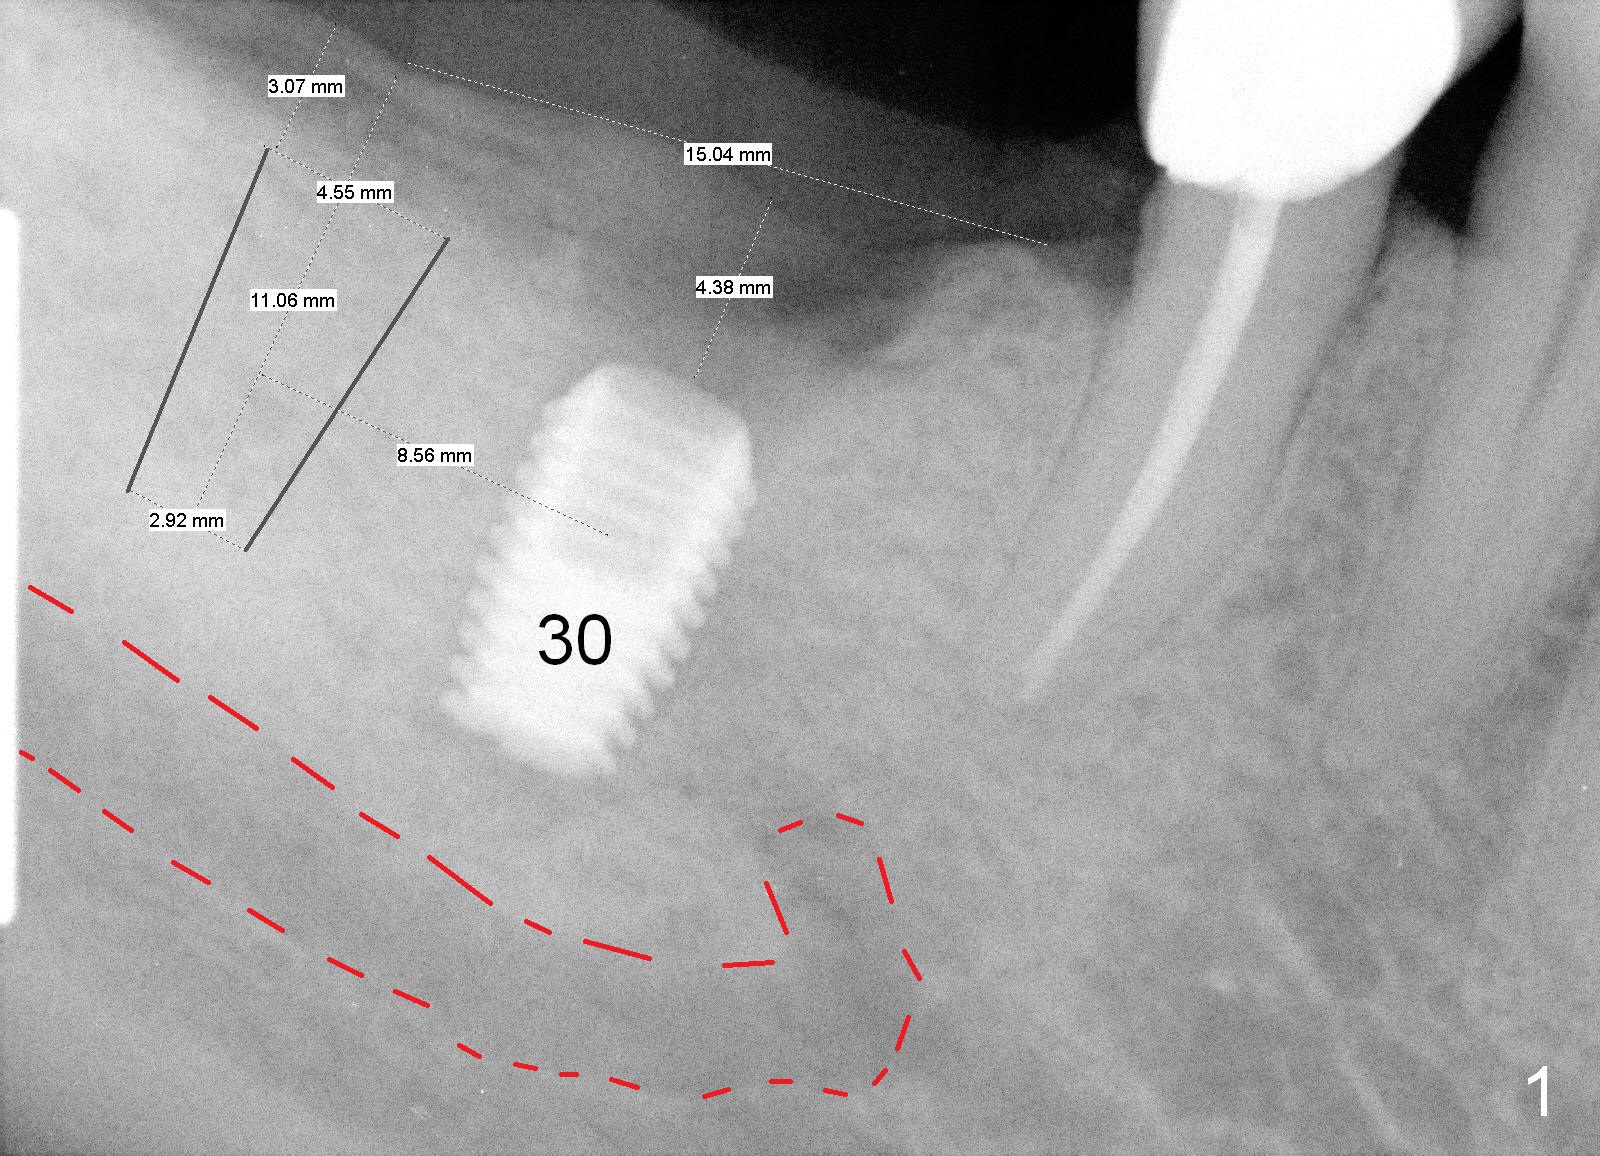

A 62-year-old man has had a Bicon abutment supported crown at #30 for nearly 2 years (Fig.1, 2 (when Tatum implant was failing)). Probably due to the fact that the implant is placed distally, there is food impaction mesially. Prior to #31 implant placement, the crown/abutment will be removed with the universal forceps and reseated. Pick up impression will be taken and sent to lab for mesial gap closure with porcelain. Take photos to show the gap preop.

Before crown removal, use the 3.5 mm (vs. normally 5 mm) implant spacer and #15 to mark an entrance point for #31 implant (make a cross over the crestal gingiva). After crown removal, insert a 3 mm Guide Pin into #30 implant well as a parallel pin. Use 2 mm pilot drill to start osteotomy through the cross and then make incision. While drilling and reaming, pay attention to the submandibular fossa (Fig.3 SF) and the Inferior Alveolar Canal (orange). When a 4.5x8 mm implant is placed, place abutments and make splinted provisional.